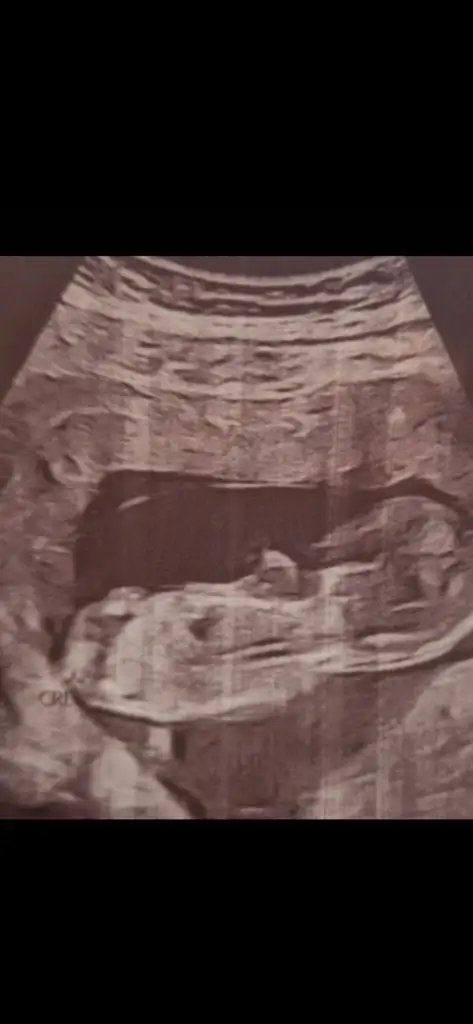

9 hafta 4 günlüklerYaa ilk kez iki keseli görüntü görüyorumtahmini çok zor uzak kalıyor sanki kaç haftalıklar

9 hafta 4 günlükler

Bir kız bir erkek :)